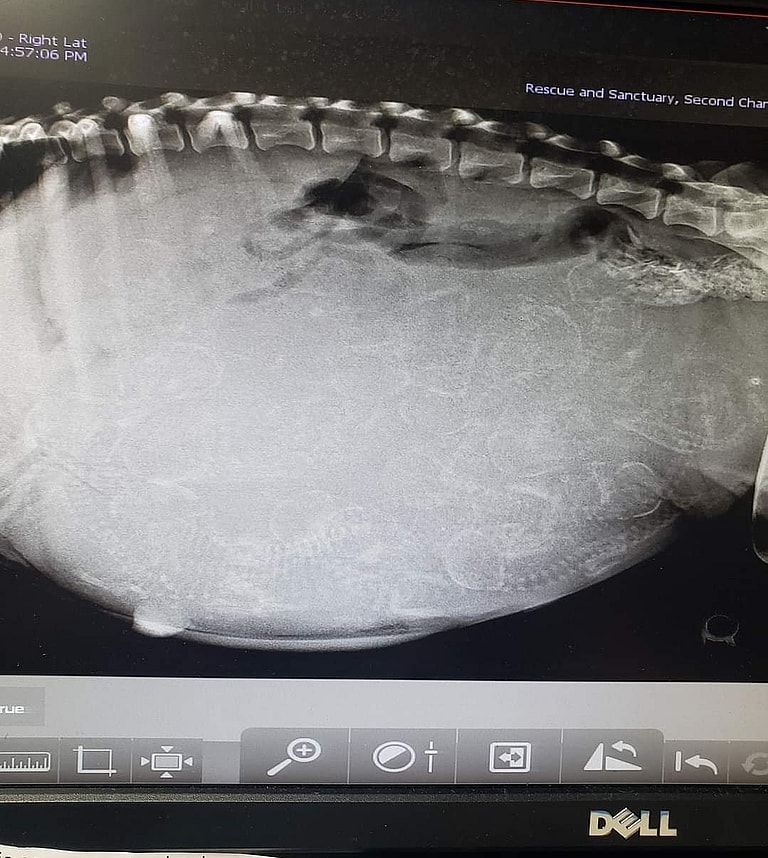

At the age of 10, Vala faced another daunting challenge: pregnancy. Just three days after arriving to Amber’s house she went into labor. “Being a mother at her age was risky,” says Amber. “Her body was not in the best condition for pregnancy.” After three emergency visits to the vet, Vala gave birth to 15 puppies, a taxing event for her already frail health. Tragically, only six of the puppies survived, likely due to her age, her health conditions and the toll that her previous life had taken on her.